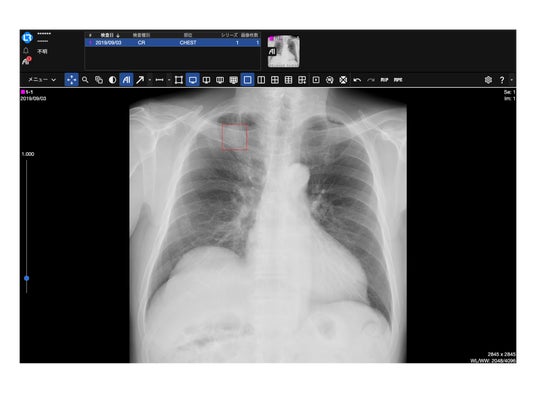

製品表示例:「AI」ボタンをおすとEIRL解析結果が表示されます。

LOOCRECを導入されている医療施設では、画像データのダウンロード・アップロード作業を伴うことなく、自動でデータが送受信・解析されることから、シームレスに画像診断支援AI「EIRL」シリーズを利用いただけます。

本連携では、胸部X線を対象としたEIRL Chest XR(※2)あるいはEIRL Chest Nodule(※3)に加え、頭部MRAを対象としたEIRL Brain Aneurysm(※4)の利用が可能となり、診断支援AI活用の選択肢がより広がります。